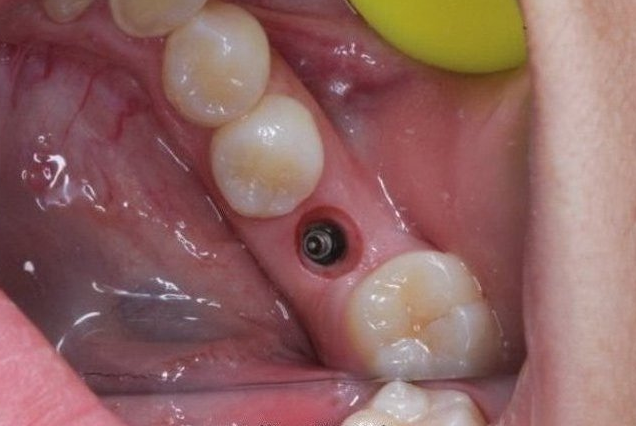

3个月后,牙龈愈合良好,袖口长的相当好